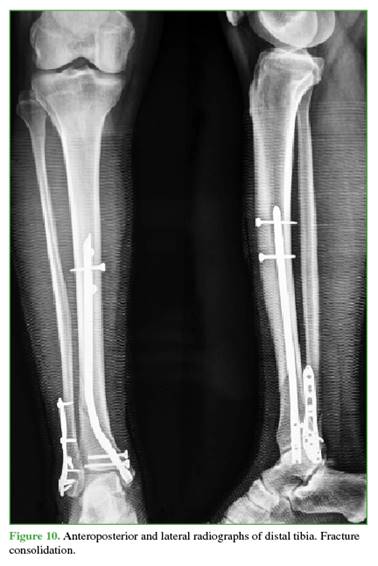

The nail of the preselected length is inserted under fluoroscopic guidance and anchored distally using the external targeting device, and proximally using a free-hand technique (Figures 8-10)

In 8 cases, fracture healing occurred by 4 months postoperatively; in the remaining 7 cases, healing was achieved by 5 months (RUST score 12).

No angular deformities were observed in the distal tibia after consolidation. According to the AOFAS scale, outcomes were excellent in 12 cases and fair in 3, one of which involved the patient with the type IIIB open fracture requiring soft tissue reconstruction (Table).